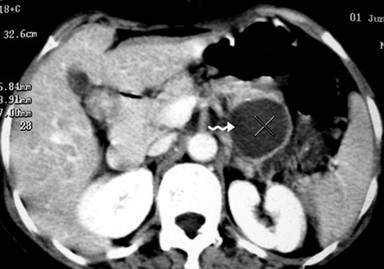

Plain X-ray of the abdomen revealed classical curvilinear calcification in only one patient with a hydatid cyst in the pancreatic body (Figure 1). Ultrasonographic examination which recorded the site, size and extent of the lesions, documented the cystic lesions as anechoic rounded structures in all cases. An abdominal CT scan documented the cysts as spherical hypodense space-occupying lesions. All the lesions were solitary, measuring 26-50 mm in diameter (mean 36.7 mm). Five lesions were cystic with thin walls and one lesion appeared as a multiseptated cyst. Magnetic resonance imaging for defining the lesion and its relationship with the pancreatic duct was performed in three patients (two lesions in the head and one in the body of the pancreas). Two lesions were located in the head (Figure 2, 3, 4, 5), two in the body (Figures 6 and 7) and two in the tail region of the pancreas (Figure 8). In two cases, a preoperative diagnosis was possible due to the presence of classical features which also included a concomitant hydatid cyst in the liver in one patient. All patients underwent surgical exploration; intraoperative cyst puncture for aspiration cytology was successful in three cases (two cases with cysts in the head and one case with a cyst in the body of the pancreas); the results of cytological examination were positive in all cases. A fragmented laminated membrane was observed in two patients, scoliosis in three and hooklets in one patient (Figure 9). The laminated membrane was seen as a foliated, acellular, pale, eosinophilic structure which stained strongly positive with periodic acid Schiff staining and negative with alcyan blue staining. The hooklets had a characteristic shape presenting as a blade, a guard and a root. They were not stained with Papanicolaou stains and their appearance was enhanced by turning down the microscope condenser. There were no complications after diagnostic aspiration. In all three cases, the aspirated fluid was colorless and contained a mean sodium level of 128 mEq/L (range: 128-130 mEq/L), chloride level of 69 mEq/L (range: 65-70 mEq/L) and potassium level of 5.8 mEq/L (range: 5.4-6.3 mEq/L). Cysts in the distal pancreas observed in the two patients were treated by a distal pancreatectomy with splenectomy. Cysts in the body were treated by a pericystectomy in one patient (Figure 10) and a central pancreatectomy in another patient. Cysts in the head region in two patients were treated with evacuation, partial cystectomy and tube drainage of the cavity after protecting the surgical area with a scolicidal solution (Figure 11). Both patients underwent T-tube drainage of the common bile duct; there was rapid regression of the jaundice in these patients. The T-tube cholangiogram confirmed the free flow of bile into the duodenum; the tubes were eventually removed in the third postoperative week. Postoperative confirmation of the hydatid cysts was obtained on the basis of the histopathological findings. There were no postoperative complications; all patients recovered uneventfully. The antihelminthic drug, albendazole, was administered postoperatively (10 mg/kg body weight/day) in all cases for a period of 6 months. All the patients were followed up at three-month intervals and each patient underwent clinical examination, abdominal ultrasonography and indirect hemagglutination tests; no patient had cyst recurrence or dissemination. The mean follow-up time was 58.7 months (range: 4-120 months).

Figure 2. Contrast-enhanced computed tomography scan showing whorled appearance of a hydatid cyst in the region of pancreatic head (thick arrow) causing atrophy of the pancreatic parenchyma with a dilated duct (arrow head) anterior to the splenic vein (curved arrow). Note another hydatid cyst in segment VI of the liver with separation of the membranes (thin arrow) (Patient #5). |

Figure 4. Contrast-enhanced computed tomography scan of the abdomen demonstrating a solitary cystic lesion (50 mm) in the pancreatic head. Note the distended gall bladder (Patient #6). |

Figure 6. Contrast-enhanced computed tomography scan demonstrating a solitary cystic lesion (33 mm) in the body of the pancreas with internal daughter cysts (Patient #3). |

Figure 7. Computed tomography scan of the abdomen revealing a rounded cystic lesion in the body of the pancreas with a ring calcification in its wall (Patient #2). |